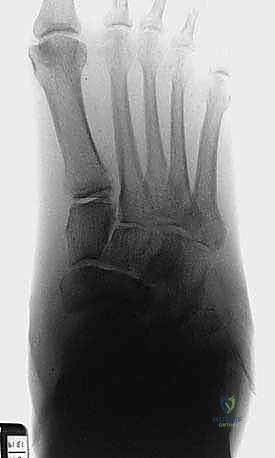

الخطوة الأولى: التخطيط الجراحي الدقيق

قبل دخول غرفة العمليات، يتم إجراء فحوصات شاملة تشمل الأشعة السينية، الأشعة المقطعية ثلاثية الأبعاد (3D CT Scan) لفهم خريطة العظام المتفتتة، وتقييم شامل للدورة الدموية (Doppler Ultrasound) لضمان وصول دم كافٍ لالتئام الجروح.